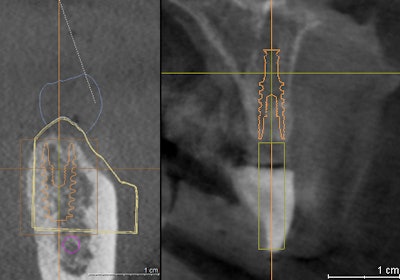

Implant plan prosthetically driven, left image under proposed Cerec crown and right image under radiopaque crown.

Implant plan prosthetically driven, left image under proposed Cerec crown and right image under radiopaque crown